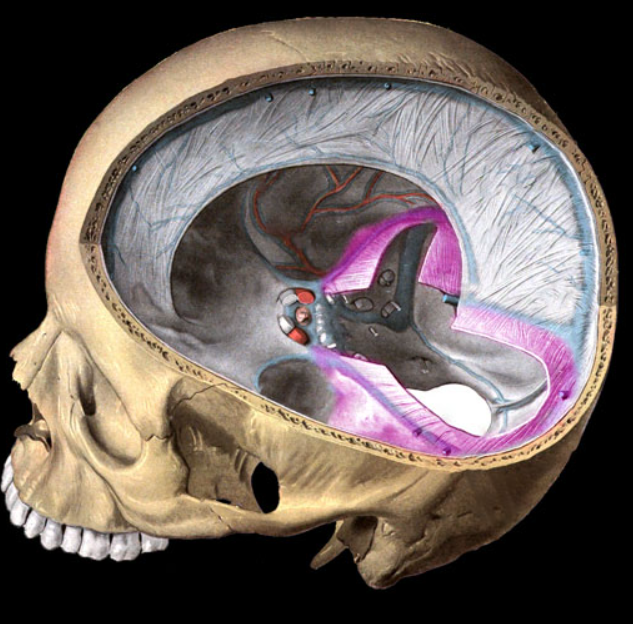

falx cerebri

falx cerebelli

tentorium cerebelli